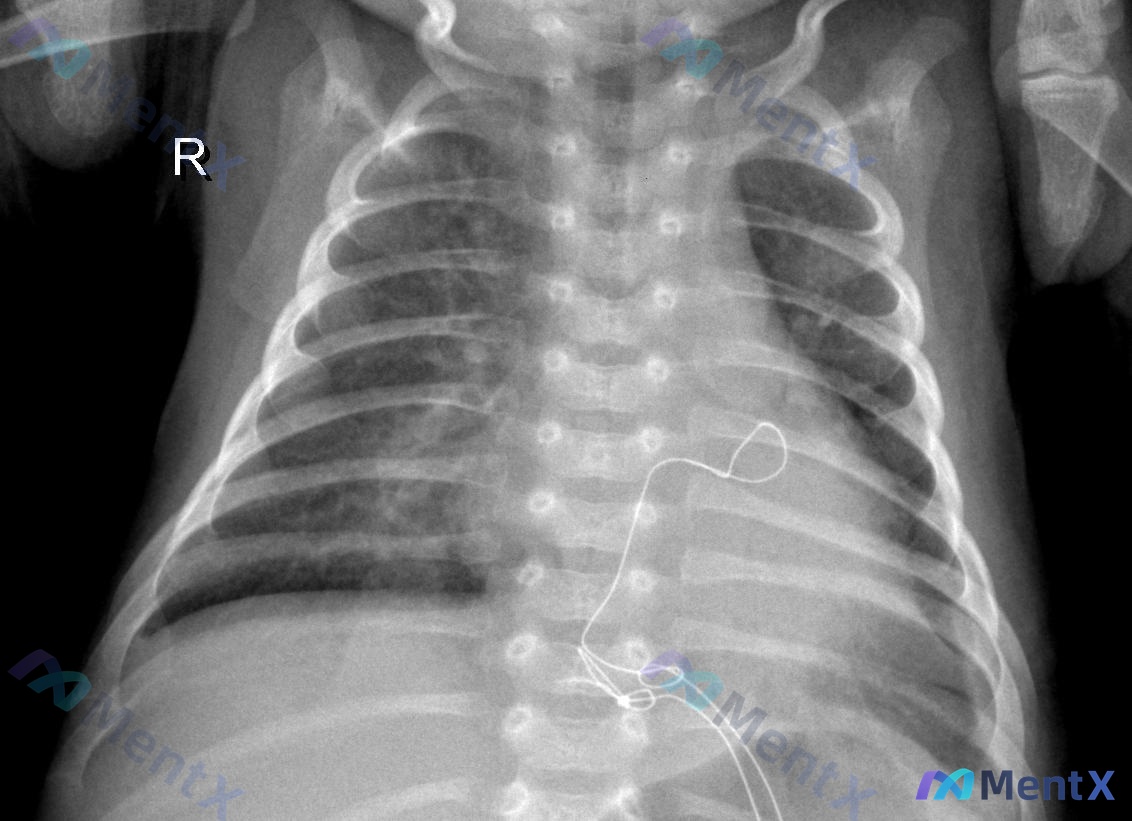

整理到一份儿科胸部正位X光片的资料和分析,觉得特别适合拿出来讨论阅片思路。 先列一下核心的影像信息: - 患儿是仰卧位(AP位)拍摄,吸气程度欠佳,曝光适中 - 左侧胸壁有圆形金属密度影(考虑监护导联),左侧腋下有导线投影 - 主要阳性发现:双肺纹理增多、增粗,以双肺门周围及内中带为著,可见斑片状密...

整理到一份儿童胸部X光片的放射分析资料,先把核心影像表现放出来,大家第一眼思路会怎么走? 基础影像背景: - 儿童患者,仰卧位AP位拍摄 - 吸气不足(第6-7后肋水平) - 有监护导线/电极片伪影 主要异常表现: - 双肺纹理增多、增粗、模糊 - 双侧肺门区及肺内带见广泛斑片状、云絮状高密度影,边...